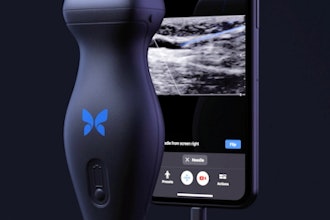

Butterfly Network secures ISO 27001 certification

October 27, 2025